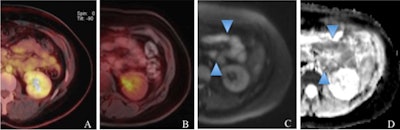

A 39-year-old woman with a histologically verified MALT lymphoma of the small intestine. The color-coded, fused FDG-PET/CT (A) and FDG-PET/MRI (B) show no increased tracer uptake. However, the DWI image (C) and the corresponding ADC map (D) clearly demonstrate the extranodal lymphoma involvement (light blue arrowheads in C and D). Images courtesy of Dr. Chiara Giraudo.

A 39-year-old woman with a histologically verified MALT lymphoma of the small intestine. The color-coded, fused FDG-PET/CT (A) and FDG-PET/MRI (B) show no increased tracer uptake. However, the DWI image (C) and the corresponding ADC map (D) clearly demonstrate the extranodal lymphoma involvement (light blue arrowheads in C and D). Images courtesy of Dr. Chiara Giraudo.Image comparisons